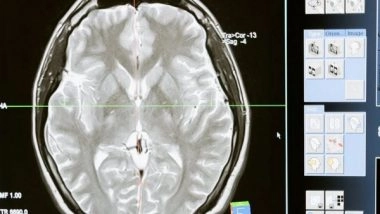

California [US], January 1 (ANI): A research team led by the University of California, Irvine has discovered a relationship between Huntington's disease mutation and developmental deficits in the brain's oligodendrocyte cells brought on by irregularities in metabolism. They found that high doses of biotin and thiamine can bring normal functions back.

OL cells generate the insulating coating around neurons, called myelin. The study, published online in the journal Nature Communications, provides detailed insight into the entire process of how these changes in the genes that regulate cell metabolism impair the development of OLs, as well as the therapeutic value of treating HD with high doses of thiamine and biotin. Thiamine and biotin are both B vitamins and are involved in a wide range of metabolic processes that help keep the nervous system healthy.

Using advanced modeling methods, researchers confirmed that in mouse and human HD brain tissue, the maturation state of OL cells and their precursors are arrested in intermediate development, impairing production of the myelin that is critical for neuronal health and function. They found that high doses of thiamine and biotin were connected to significant rescue of gene expression changes in OL cells.